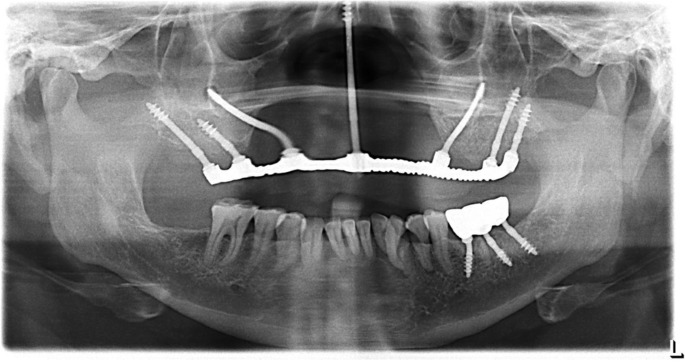

Elevate your dental care journey with our membership program, specifically designed for patients seeking teeth implants. As a member, you’ll benefit from reduced pricing on implant procedures, priority scheduling for consultations and treatments, and continuous follow-up care to ensure the best outcomes. Join today to access top-tier dental implant services and enhance your smile with confidence.